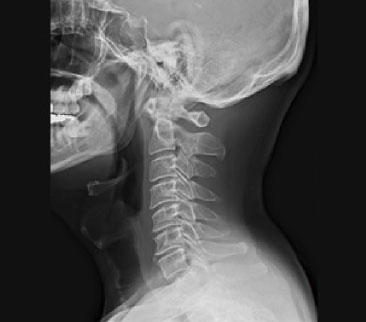

一般撮影

一般撮影とは

一般撮影は、レントゲン検査やⅩ線撮影と呼ばれることもあり、胸部、腹部、骨など全身各部位の撮影を行います。

Ⅹ線という放射線を人体に照射して透過したⅩ線を画像にします。

検査時間は、部位や撮影回数により異なりますが5~10分程度です。

頸椎